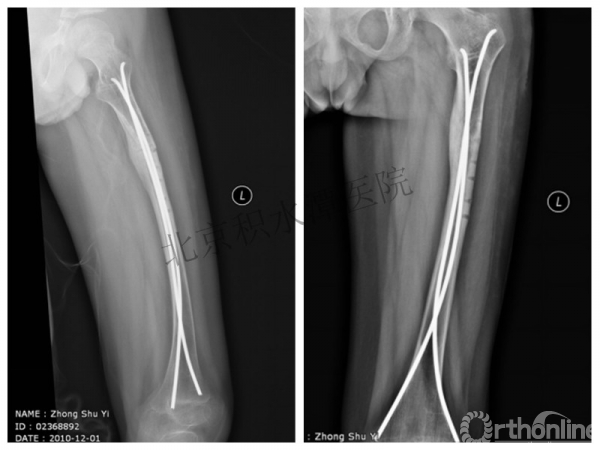

病例分享五

女孩、6岁,股骨干骨折

原始损伤

牵引后4周

伤后18月

没有任何外观和功能障碍!相信每位小儿骨科医生都会有很多类似的病例!除非您不承认或者没有认识到塑形!

儿童骨折的基本特点—塑形!

1.充分利用此特点

2.不要人为地破坏

3.不要好心办坏事